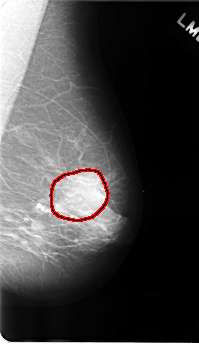

C_0177_1.LEFT_MLO

LEFT_MLO LINES 4880 PIXELS_PER_LINE 2776 BITS_PER_PIXEL 12 RESOLUTION 50 OVERLAY

FILE: C_0177_1.LEFT_MLO.OVERLAY

TOTAL_ABNORMALITIES 1

ABNORMALITY 1

LESION_TYPE MASS SHAPE ROUND MARGINS ILL_DEFINED

ASSESSMENT 4

SUBTLETY 5

PATHOLOGY MALIGNANT

TOTAL_OUTLINES 1

BOUNDARY